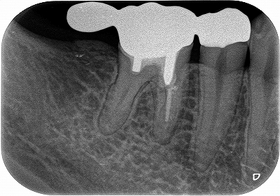

2026 EEdental FUD (3).jpg

この後遠心根抜歯

2026 EEdental FUD (4).jpg

口腔外科で移植をしてもらい、移植歯の根管治療を行い

2026 EEdental FUD (5).jpg

ある程度咬めるように治させてもらいました。

今年になり患者さんが詰め物が外れたとのことで来院

2026 EEdental FUD (6).jpg

10年経過して、そこまで悪い感じはありません。

患者さんにも「先生にそんなに持たないかもしれないよと言われていましたが10年持っています。意外と持つものですね!」と言われましたが、

ホント最初の延長ブリッジの方がかなり良い条件でしたが、折れてしまった。

パフォレーション+分割抜歯、移植した歯という条件の悪いケースで10年経過している。。。